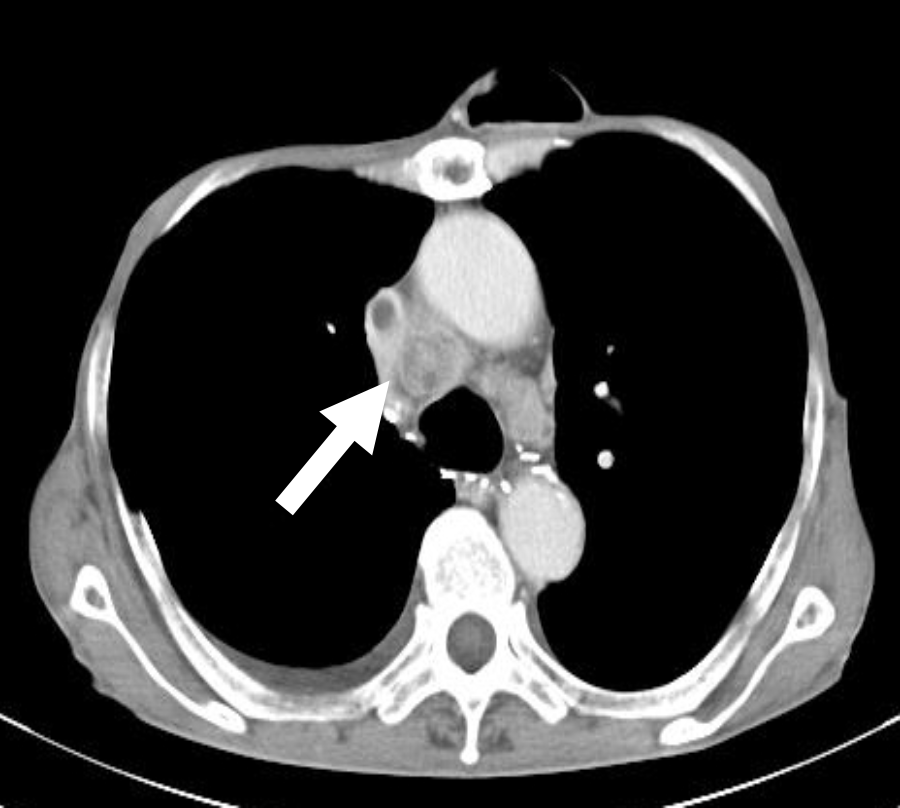

Ct検査よりがん組織と正常組織の区別が明確でct検査とは異なる情報からがんの深さや広がりリンパ節への転移の有無を調べます 7超音波エコー検査 首の表面から超音波をあ てそのはね返りをモニターで見ながら確認. 下咽頭癌の進展範囲を読影する際のチェックポイント 腫瘍の最大径 喉頭への進展の有無 軟骨浸潤の有無 上下方向への進展範囲の決定中咽頭頸部食道 軟部組織浸潤の有無特に梨状癌 梨状窩尖部への進展の有無.

頸部 Dual Energy Ctを用いた喉頭癌と下咽頭癌による喉頭軟骨浸潤評価